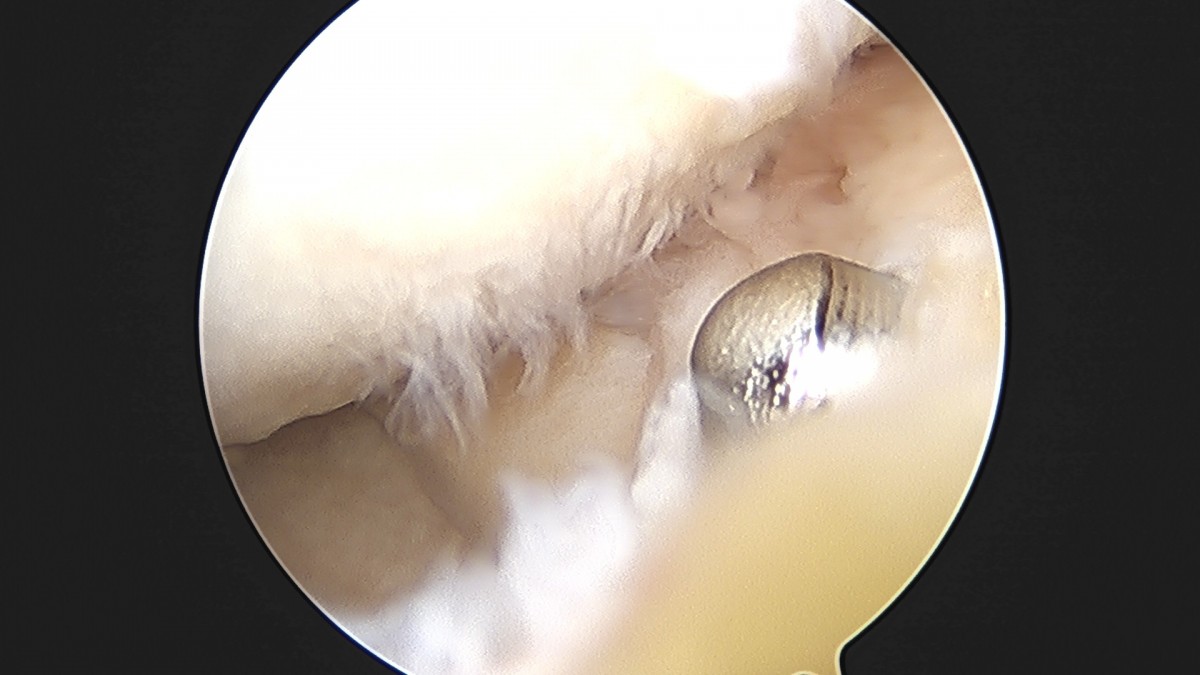

이재상원장님 무릎 반월상 연골판 절제술 박민O 환자

작성자 최고관리자 댓글 0건 조회 382회 작성일 25-09-16 15:46